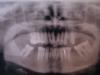

Bier Опубликовано 5 ноября, 2008 Поделиться Опубликовано 5 ноября, 2008 ну если он будет несъемным - он не восстановит отсутсвующие жевательные зубы, разве что консоль туда сделают (что неправильно) надо понять несколько вещей, а то у вас каша в голове1. Протезироваться надо, т.к. вашей маме по сути нечем жевать.2. Мертвые зубы необходимо закрыть коронками.(но если посмотреть на снимок, то у вашей мамы на верхней челюсти всего 3 живых зуба, на двух из них я хорошо вижу кариес, т.е. их возможно тоже уже пора депульпировать и закрывать коронками. Остается 1 живой зуб. Его конечно можно оставить и так, но это будет совсем некрасиво, т.к. новые коронки будут явно от него отличаться, сомневаюсь, что у вашей мамы он выглядит как у 20ти летней девушки.) Отсюда следует, что доктор, смотревший вашу маму не так уж и неправ.3. Для восстановления отсутсвующих жевательных зубов, вашем случае, можно прибегнуть к съемному протезированию бюгельным протезом (значит к имеющимся зубам, закрытым коронками будет крепиться съемная часть) либо поставить имплантаты и сделать на них отдельные коронки. Ссылка на комментарий